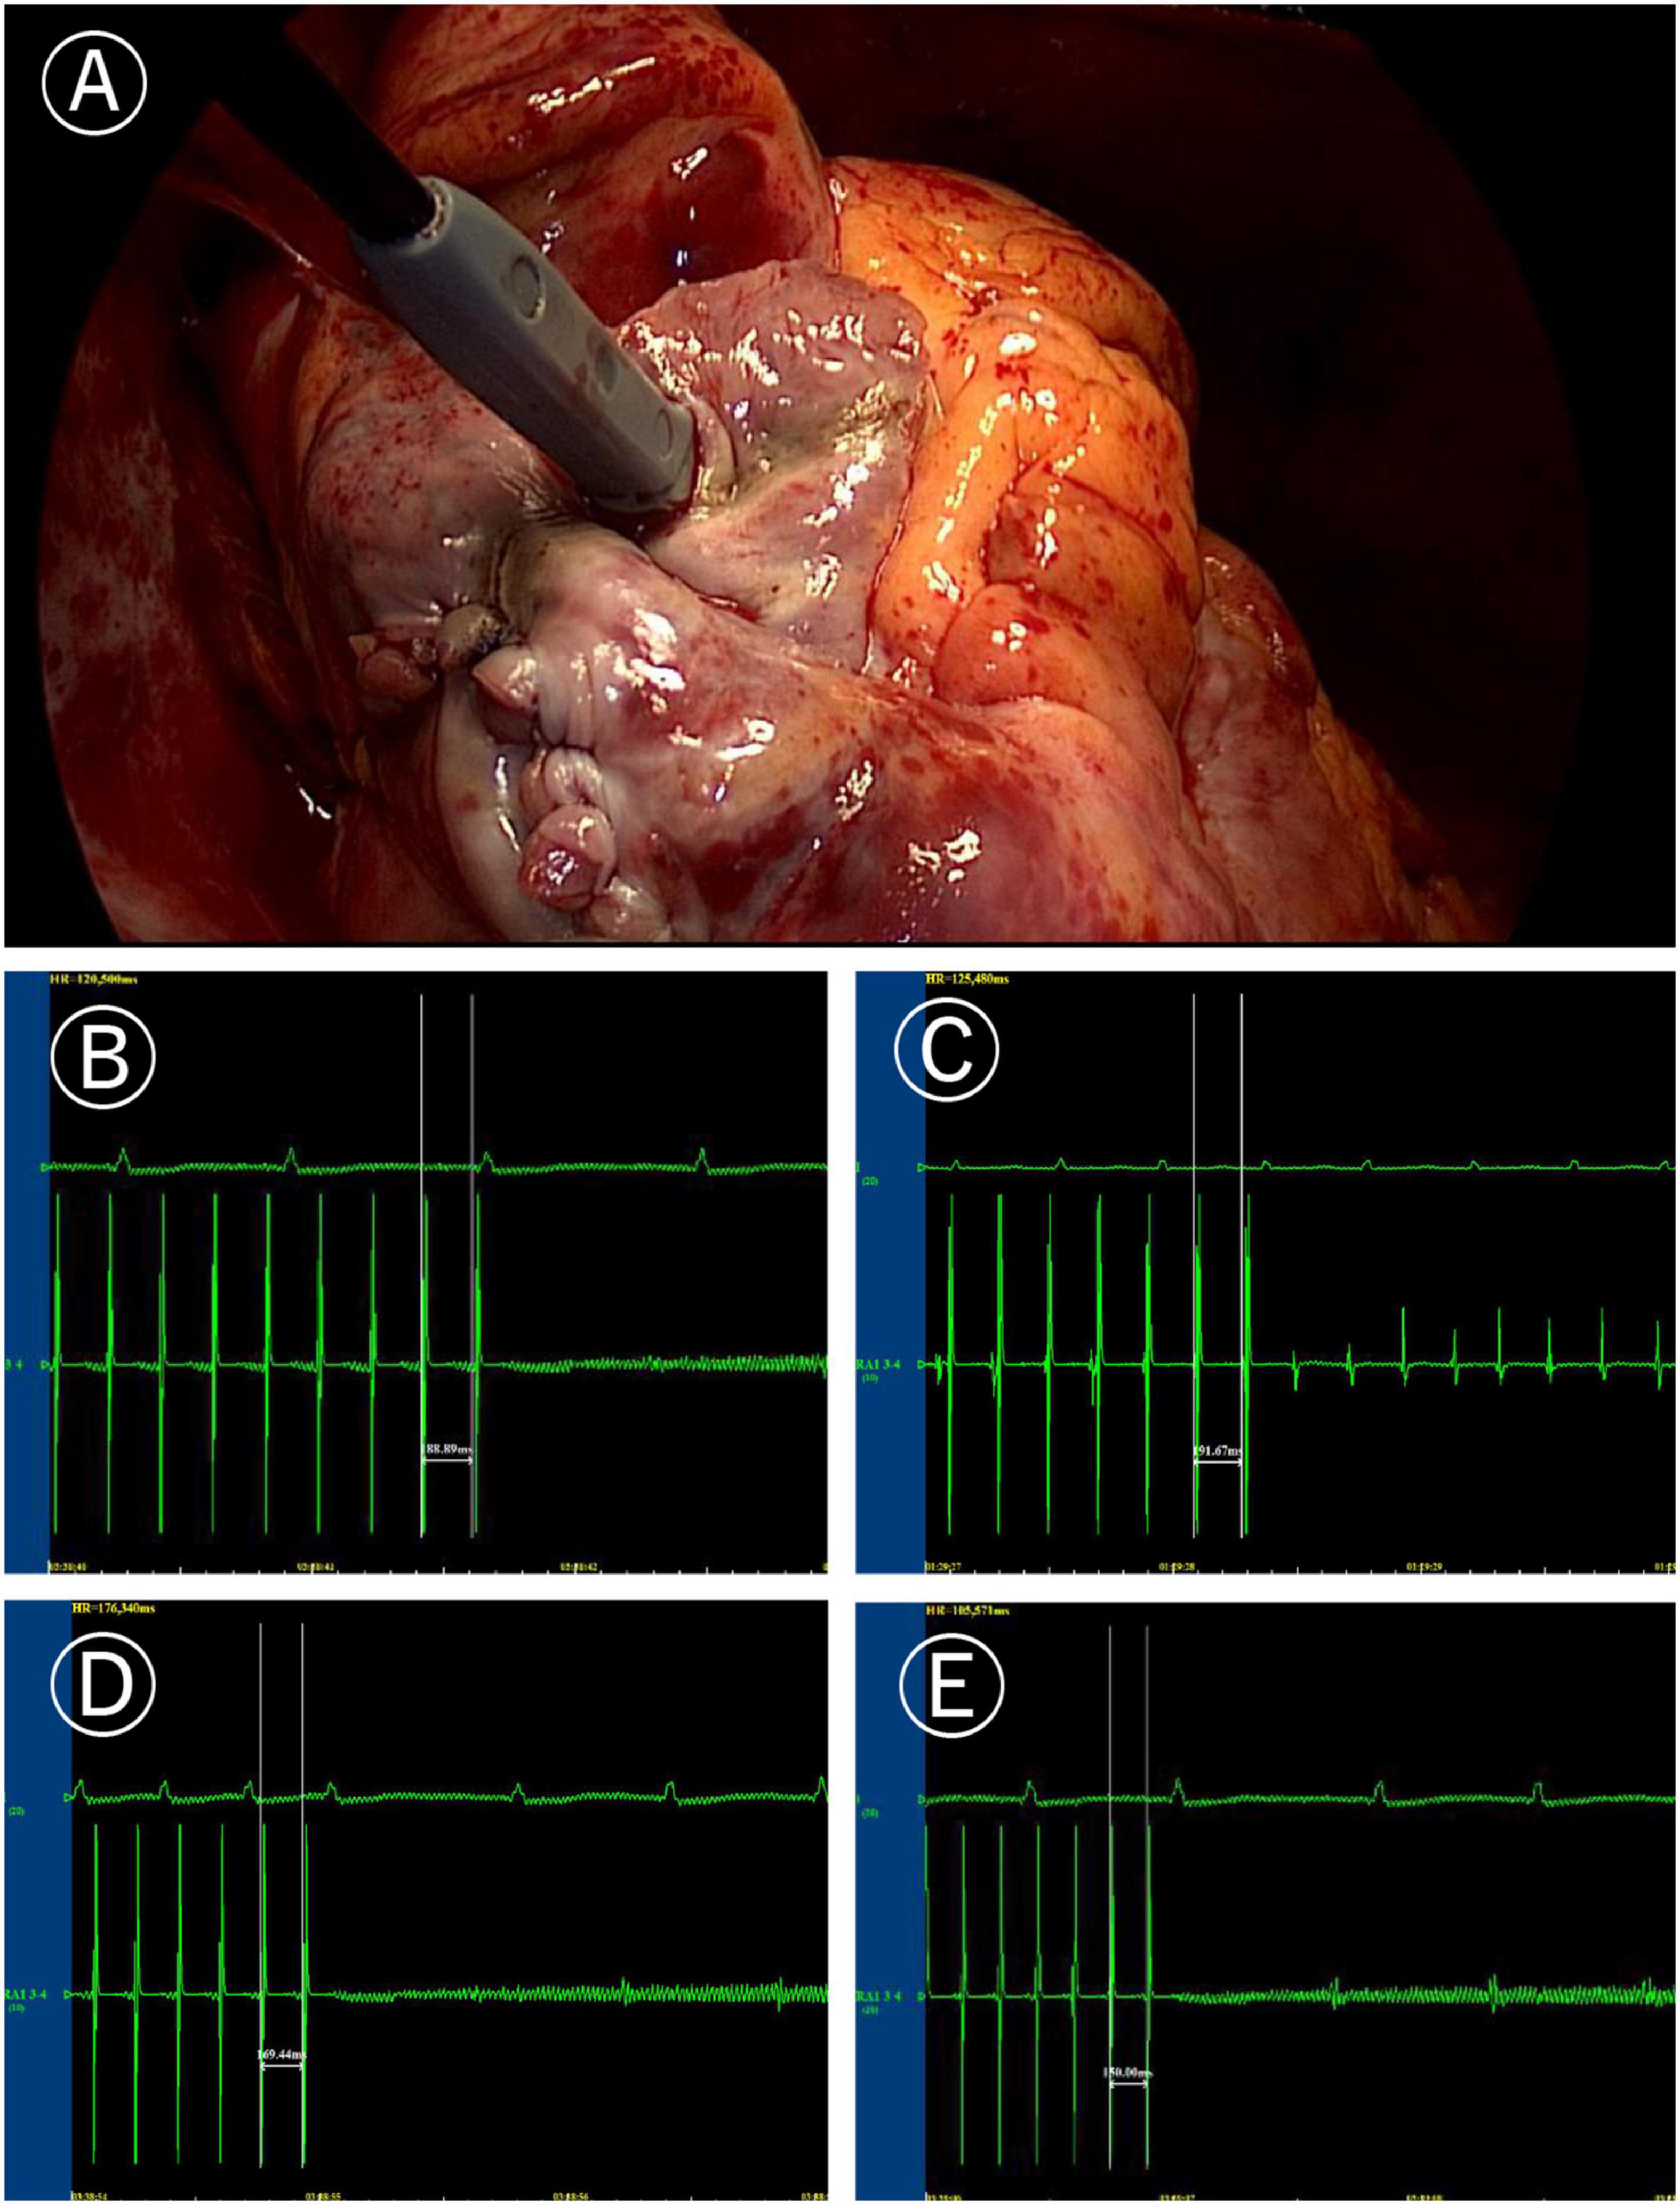

In the Electrophysio-Maze group, all patients underwent AF induction before and after the Cox-Maze IV procedure (Figure 1). The induction was performed with cannulization but without cardiopulmonary bypass, making the conditions consistent as much as possible. AF was induced in 88.1% (37/42) of all patients before Cox-Maze IV and was induced in 14.3% (6/42) of all patients after the Cox-Maze IV procedure. The bidirectional electrical isolation of the mitral annular isthmus ablation line (Figure 2), “box” ablation lines (Figure 3), and tricuspid annular ablation line (Figure 4) was successfully mapped in each patient. The rate of incomplete bidirectional electrical isolation of “box” ablation lines immediately after Cox-Maze IV was zero (the rate of complete bidirectional conduction block of “box” ablation lines immediately after Cox-Maze IV was 100%), and the rate of incomplete bidirectional electrical isolation of mitral isthmus ablation lines or tricuspid annulus ablation lines was 23.8% (10/42), wherein the rate of incomplete bidirectional electrical isolation of both mitral isthmus and tricuspid annulus ablation line was 7.14% (3/42), the rate of incomplete bi-directional electrical isolation of single mitral isthmus ablation line was 7.14% (3/42), and the rate of incomplete bidirectional electrical isolation of single tricuspid annulus ablation line was 9.52% (4/42). In two cases of incomplete bidirectional electrical isolation in single tricuspid annulus ablation line, complementary ablation was performed, and then electrophysiological mapping was performed again to ensure that the subsequent electrophysiological mapping confirmed the final complete bidirectional electrical isolation. The final incomplete bidirectional electrical isolation rate of mitral isthmus or tricuspid annulus ablation line was 19.0% (8/42). The incomplete bidirectional electrical isolation rate of ablation lines was correlated with AF inducibility immediately after Cox-Maze IV procedure but not with AF inducibility before Cox-Maze IV (Table 3).

Figure 1. Induction of atrial fibrillation (AF). (A) Image of programmed stimulation at high right atrial for induction of atrial fibrillation (post surgery). (B) AF induced by the 190 ms cycle stimulation before Cox-Maze IV. (C) After Cox-Maze IV, the 190 ms cycle stimulation failed to induce AF again. (D) After Cox-Maze IV, the 170 ms cycle stimulation could not induce AF; and (E) After Cox-Maze IV, the 150 ms cycle stimulation could not induce AF.